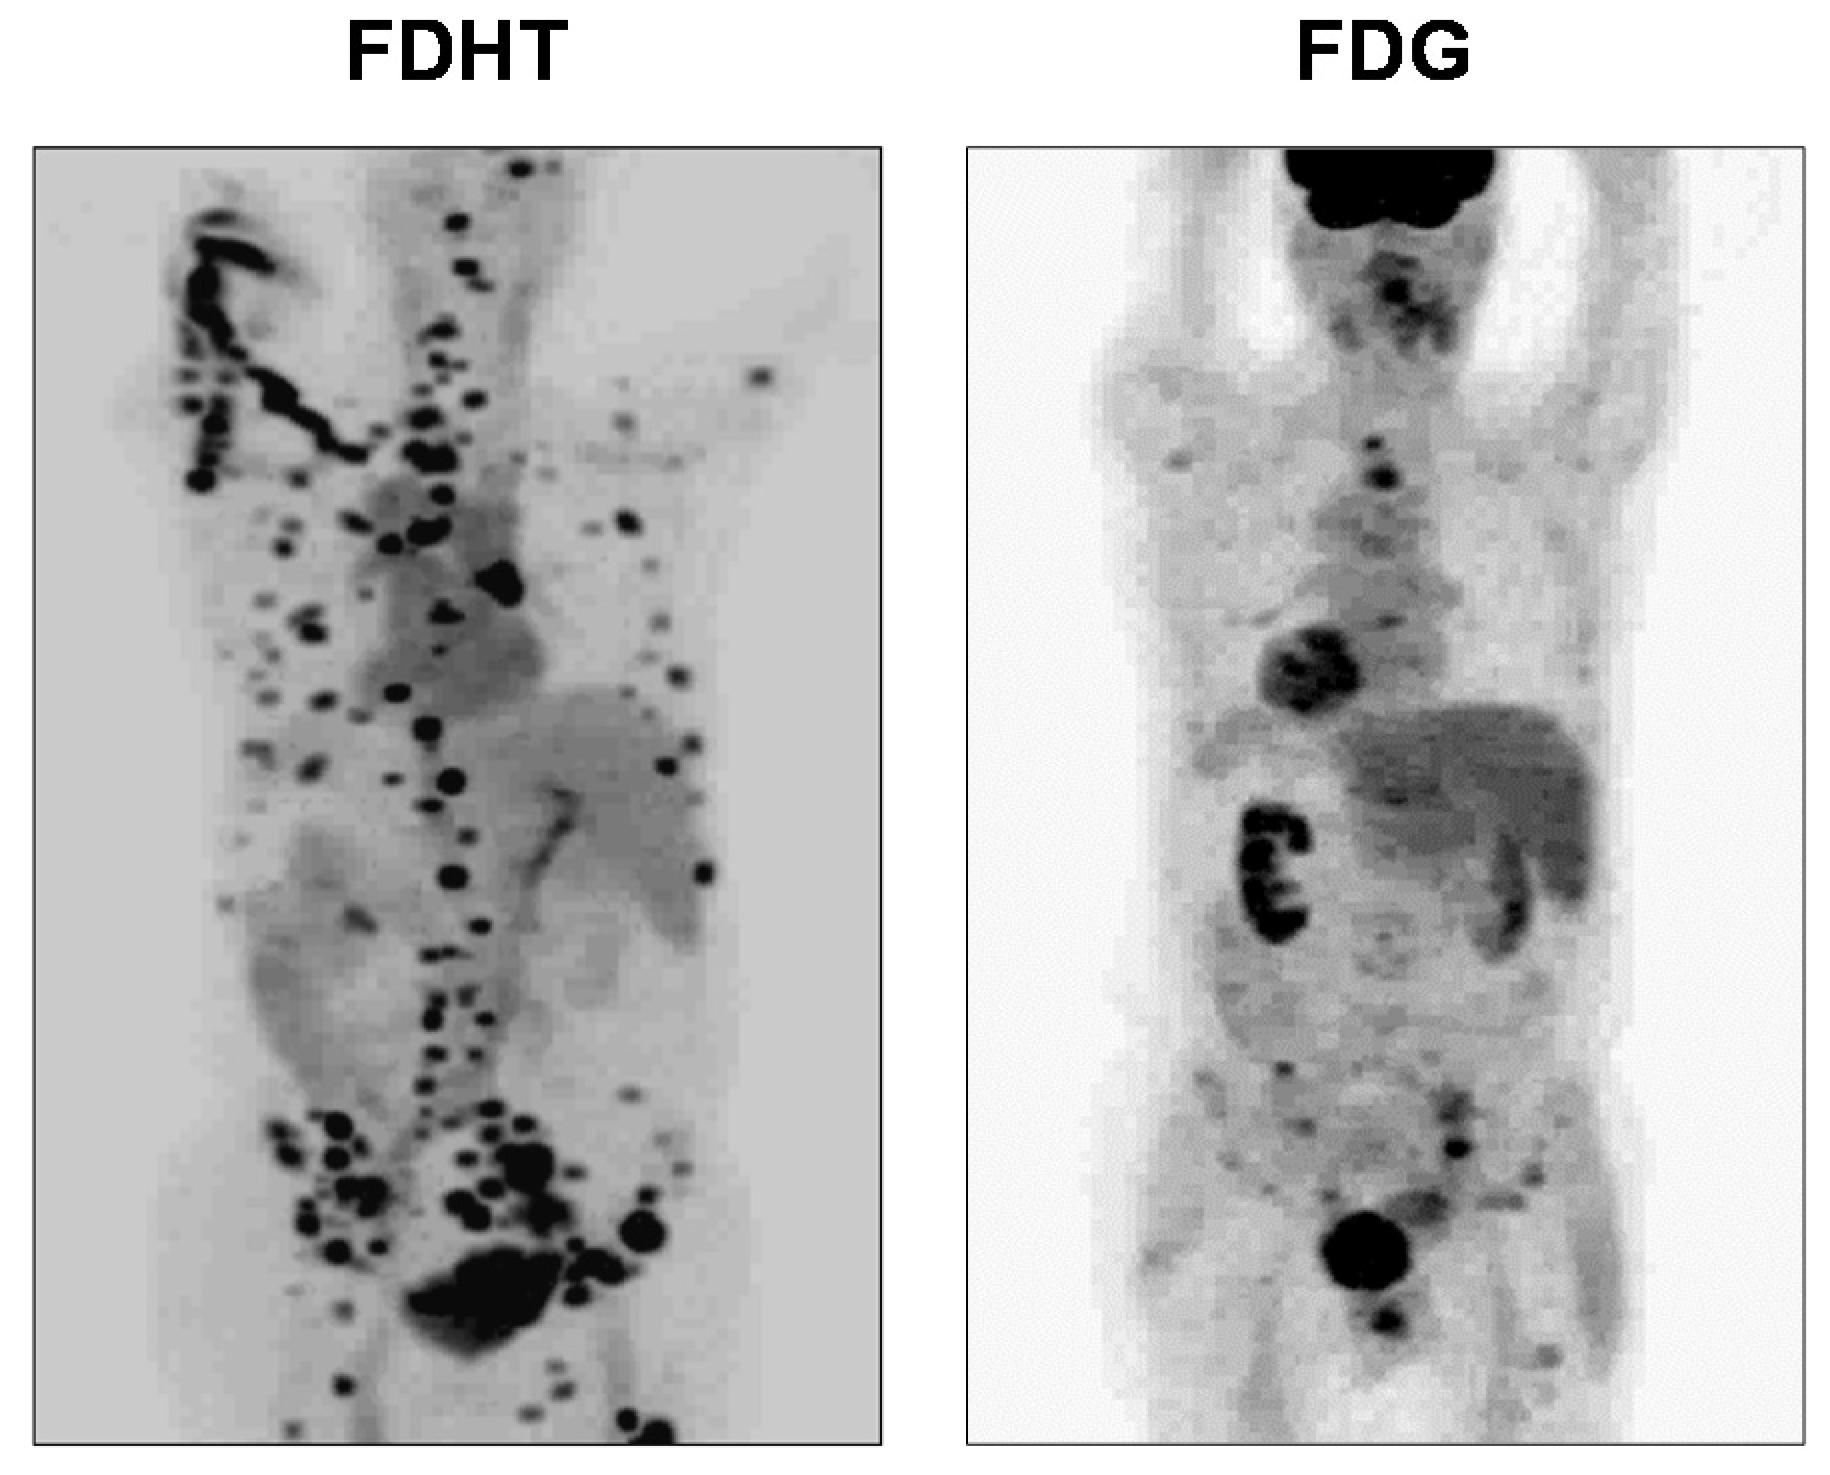

- Larson, S.M.; Morris, M.; Gunther, I.; Beattie, B.; Humm, J.L.; Akhurst, T.A.; Finn, R.D.; Erdi, Y.; Pentlow, K.; Dyke, J. Tumor localization of 16β-18F-fluoro-5α-dihydrotestosterone versus 18F-FDG in patients with progressive, metastatic prostate cancer. J. Nucl. Med. 2004, 45, 366–373. [Google Scholar]